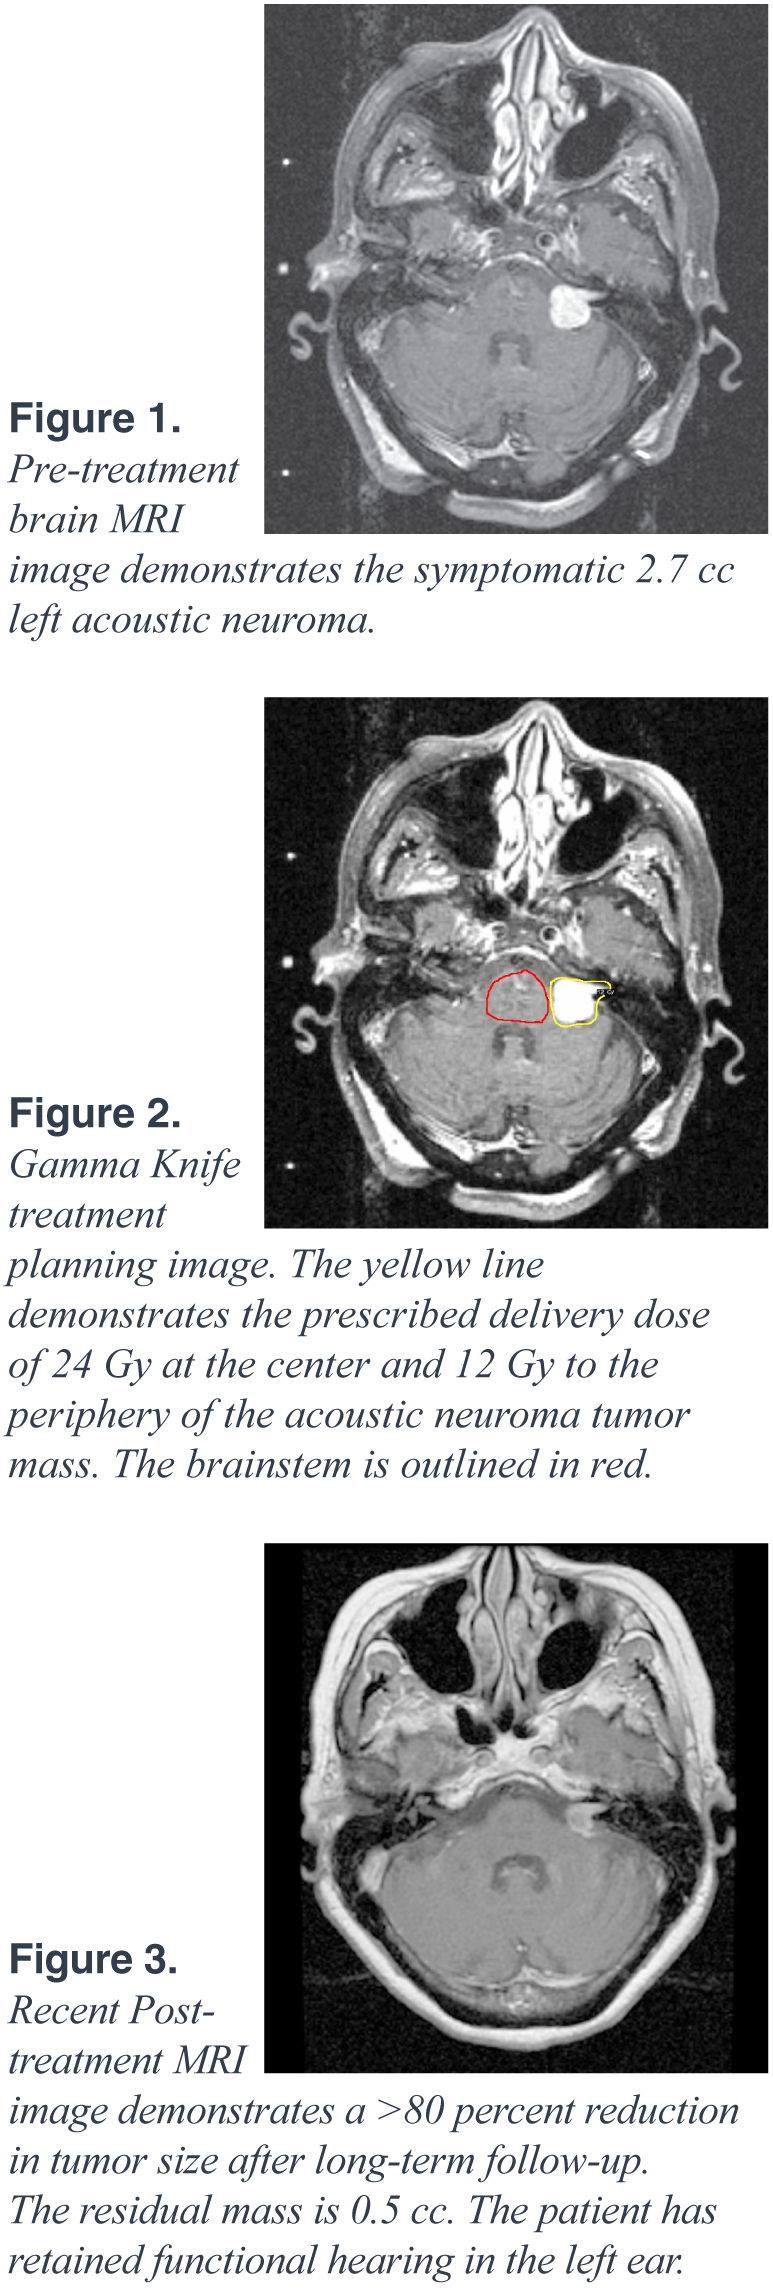

The patient is a 75-year-old female who presented to Neurosurgeon Dr. Asher Taban, MD, and Radiation Oncologist Afshin Safa, MD, with a five-year history of left-sided tinnitus and progressive sensorineural hearing loss. An MRI of the brain was performed, which revealed a 2.7 cc left-sided enhancing mass compressing the brainstem and extending from the left internal auditory canal into the cerebellopontine angle region. The radiographic features of this mass were consistent with an acoustic neuroma, which is a common benign tumor of the eighth cranial nerve. Her case was presented to our multidisciplinary Gamma Knife Review Board. Given the tumor’s size, location, and the associated symptoms of hearing loss and tinnitus, the patient underwent Gamma Knife Stereotactic Radiosurgery at Northridge Hospital Medical Center.

On the day of treatment at the Gamma Knife Center, a stereotactic head frame was fitted and a treatment planning MRI was obtained. A three-dimensional treatment plan was developed on the Gamma Knife treatment planning workstation to deliver an ablative dose of 24 Gy at the center and 12 Gy to the periphery of the tumor, while sparing the adjacent brainstem. The radiation dose was delivered using 15 discrete spherical shots to sculpt the dose to conform to the acoustic neuroma and avoid the adjacent normal structures. The Radiosurgery treatment was delivered in less than one hour. The patient tolerated the procedure well and was able to return to normal activities later that day.

We have continued to follow the patient on a semiannual basis since her Gamma Knife Stereotactic Radiosurgery. She has had improvement of her tinnitus and has retained functional hearing in the left ear. Three-years after treatment, her most recent MRI revealed a 0.5 cc residual mass with necrotic center, which represents a greater than 80 percent reduction in size, as well as diminished radiographic enhancement. The patient maintains her active life and is a world traveler. She will continue to be followed by our Gamma Knife treatment team on a semiannual basis.